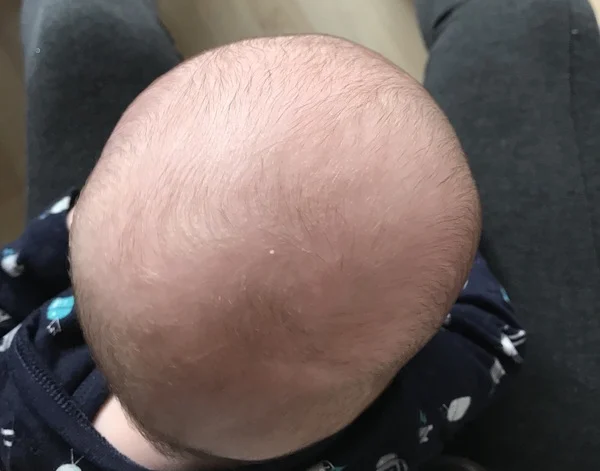

تعظّم الدروز الباكر غير المتلازمي عند الرضع: الأسباب، الأعراض والعلاج تُعدّ حالة تعظّم الدروز الباكر غير المتلازمي (Non-syndromic Craniosynostosis) من الحالات التي قد تُسبب قلقًا كبيرًا للأهل عند ملاحظتها لدى الرضيع، خاصة عندما يتغير

جراحة الدرز السهمي بالمنظار عند الأطفال: شرح كامل للعملية والنتائج المتوقعة يُعد التحام عظام الجمجمة المبكر من الحالات التي تقلق الكثير من الأهل، خاصة عند ملاحظة أن شكل رأس الطفل أصبح طويلًا وضيقًا بشكل

ما هي الحالات التي تعالجها عملية التحام عظام الجمجمة بالمنظار عند الأطفال؟ يُعد التحام عظام الجمجمة المبكر من الحالات التي تثير قلق الأهل بشكل كبير، خاصة عندما يلاحظون تغيرًا غير طبيعي في شكل رأس

جراحة التحام عظام الجمجمة بالمنظار (Endoscopic Craniosynostosis Repair): دليل شامل للأهل يُعد التحام عظام الجمجمة المبكر من الحالات التي قد تثير القلق لدى الأهل، خاصة عند ملاحظة تغيّر شكل رأس الطفل في الأشهر الأولى